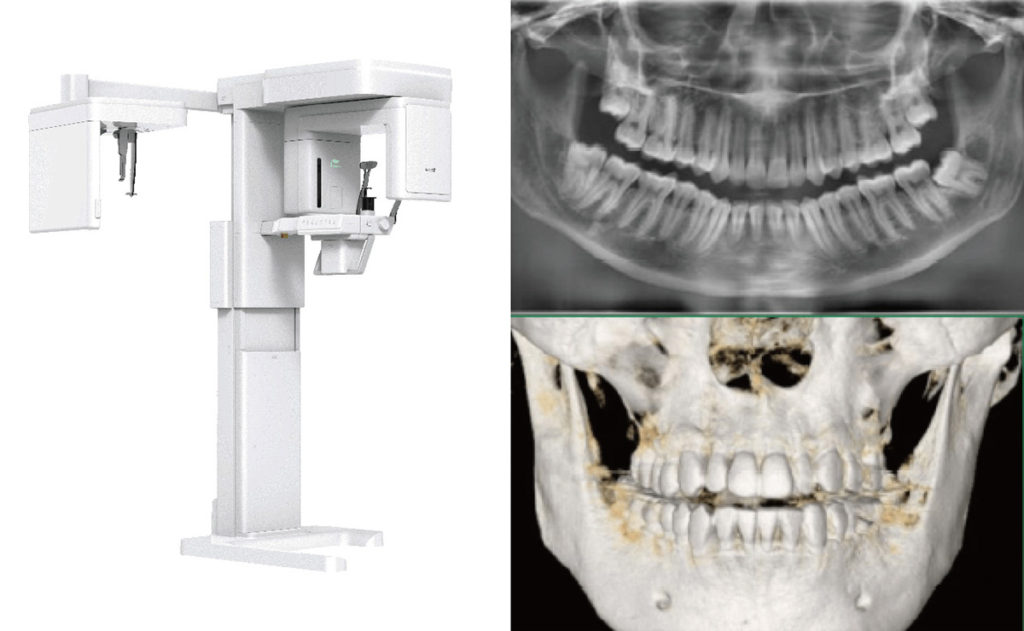

一般歯科においても普及が進んでいるパノラマ併用型CT撮影機によって取得された三次元画像は、より精密な診断と正確な治療計画の立案を強力にサポートします。

世界トップクラスのシェアを誇る、韓国発の歯科用レントゲン・CT機器メーカー『Vatech(バテック)』。今回は、その英知を集結させた「Green X 12(グリーン・エックス トゥエルブ)」を参照に解説していきます。